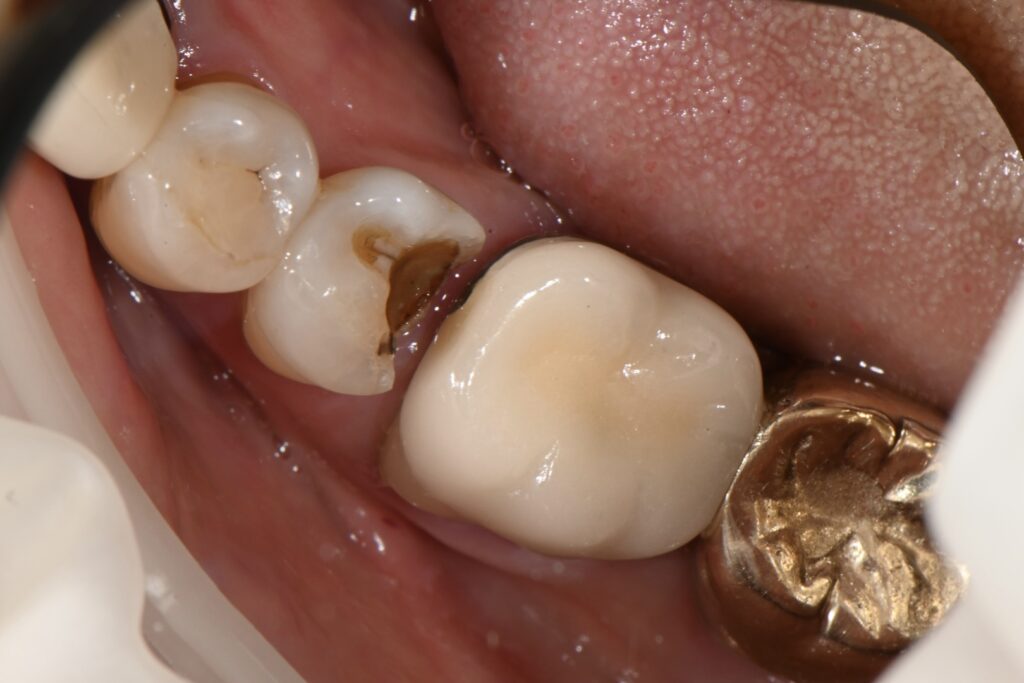

기존의 인레이가 문제가 되어서 내원을 하시었습니다

골드 인레이의 전형적인 문제점

바로 접착실패로 인하여 생기는 미세누출

그리고 미세누출로 인하여 생기는 2차충치

신경으로 이어지는 염증 전형적인 신경치료 순서를 밟아 가고 있습니다

이런 경우 통상적으로 신경치료를 진행하게 되는데요

하지만 레진빌드업이라는 치료방법은 1회의 치료로 모든 치료가 끝나게 됩니다

이미 깊은 충치를 확인할 수 있습니다

이정도면 꽤 깊은 부위인데요

거의 신경과 인접한 그런 부분입니다